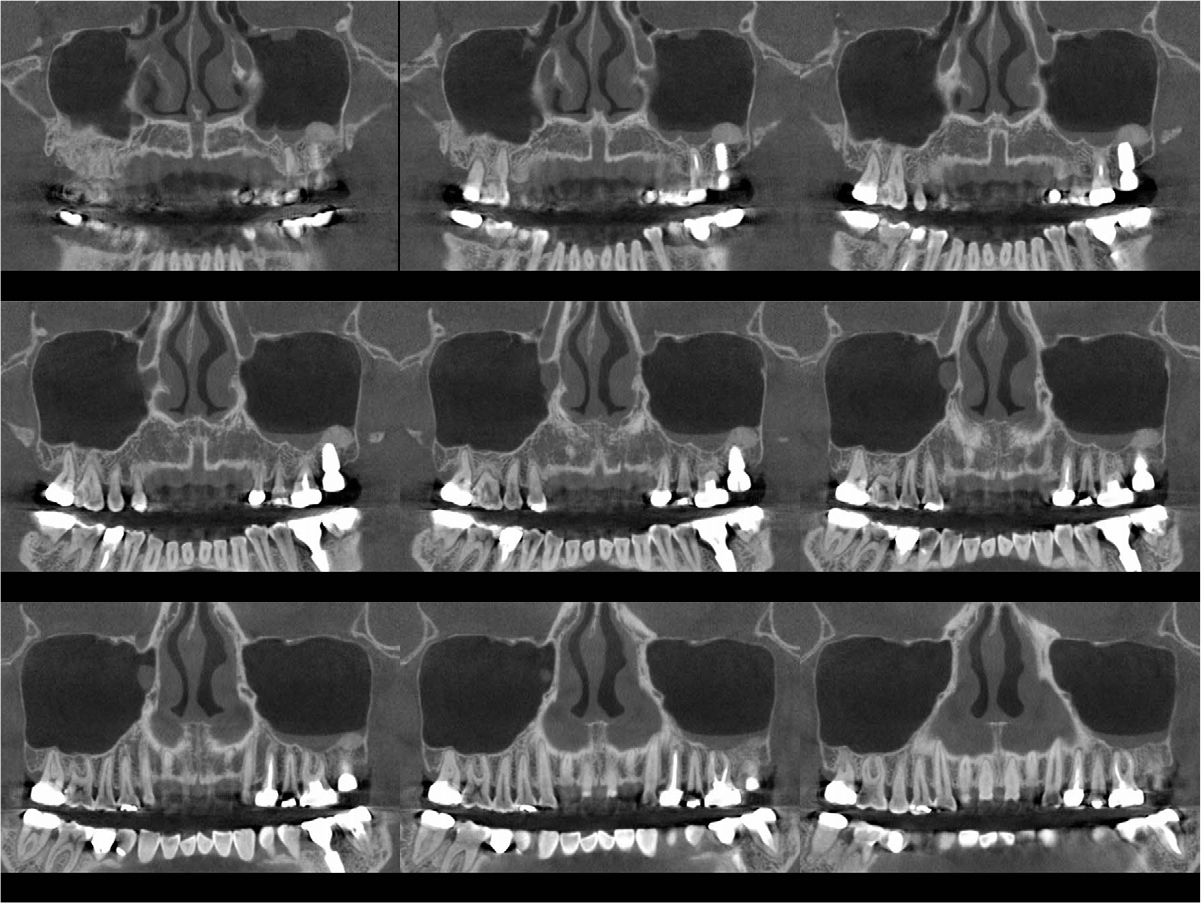

An implant with 5.0 mm diameter and 8.0 mm length (Superline; Dentium, Seoul, Korea) was placed with 0.5 cc of eproteinized bovine bone mineral (DBBM; Bio-Oss®, Geistlich, Wolhusen, Switzerland) by sinus elevation. The implant stability quotient (ISQ) after placement was 64 continually and the healing abutment was placed (6.5 mm diameter, height M size) (Fig. 4A, 4B). Postoperative antibiotics (Sultamox Tab. 500 mg; Alvogen, Seoul, Korea) and analgesics (Somalgen Tab. 370 mg; Alvogen), digestive agent (Beszyme Tab. 470 mg; Dong-A ST, Seoul, Korea) were prescribed for 5 days (30 min after meal). Gargle agent (G.U.M® Dental Rinse S; Sunstar, Osaka, Japan) with no toothbrushing was prescribed to drain and protect the operation area for 2 weeks. Postoperative cone-beam computed tomography (CBCT) showed a dome-shaped elevated membrane with a heterogeneous bone graft surrounding dental implants (Figs. 5 and 6). After 14 days, favorable healing gingiva was confirmed with the stitch-out process (Fig. 7).

Numerous studies have evaluated protocols to increase the success rate of immediate implant placement after extraction. The primary stability of immediate implant placement has been reported to be the most important factor.15 Lioubavina-Hack et al.16 presented at least 3−5 mm residual alveolar bone under the extraction socket as the requirement for successful placement. In this case, a 5 mm residual bone height would be sufficient for primary stability; however, this is not a satisfactory vertical bony height for implant placement. Therefore, the alveolar crestal approach and hydraulic sinus lift technique with DBBM were used for the elevation of the maxillary sinus membrane. As favorable primary stability was guaranteed, the healing abutment was placed consecutively. The sinus membrane was not elevated symmetrically, as ordinary in the case of hydraulic sinus lift, but the fixture was surrounded by sufficient bone graft material verified by CBCT (Fig. 6).

Previous studies have evaluated the positional relationship between the surrounding bone and the fixtures. Vignoletti et al.17 and Caneva et al.18 have reported that buccal bone resorption was significantly lower in the case of implants placed close to the lingual wall. Chen et al.19 also reported that a bone graft between the fixture and the buccal wall, in case of sufficient residual buccal bone thickness, could inhibit horizontal bone resorption; however, vertical bone resorption would be inevitable. In this case, more than 2 mm of residual buccal bone and fixtures placed close to the lingual wall are confirmed by CBCT (Fig. 6). These findings would guarantee favorable surrounding alveolar bone volume after 4 years of implant placement.